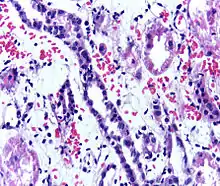

People with ESRD who receive a kidney transplant generally live longer than people with ESRD who are on dialysis and may have a better quality of life.[1] However, kidney transplant recipients must remain on immunosuppressants (medications to suppress the immune system) for as long as the new kidney is working to prevent their body from rejecting it.[1] This long-term immunosuppression puts them at higher risk for infections and cancer.[3] Kidney transplant rejection can be classified as cellular rejection or antibody-mediated rejection. Antibody-mediated rejection can be classified as hyperacute, acute, or chronic, depending on how long after the transplant it occurs. If rejection is suspected, a kidney biopsy should be obtained.[3] It is important to regularly monitor the new kidney's function by measuring serum creatinine and other labs; this should be done at least every three months.[3]

Acute rejection is another possible complication of kidney transplantation; it is graded according to the Banff Classification which incorporates various serologic, molecular and histologic markers to determine the severity of the rejection. Acute rejection can be classified as T-cell mediated, antibody mediated or both (mixed rejection). Common causes of acute rejection include inadequate immunosuppression treatment or non-compliance with the immunosuppressive regiment.[72] Clinical acute rejection (seen in approximately 10-15% of kidney transplants within the first year of transplantation) presents as kidney rejection with associated kidney dysfunction.[72] Subclinical rejection (seen in approximately 5-15% of kidney transplants within the first year of transplantation) presents as rejection incidentally seen on biopsy but with normal kidney function.[72] Acute rejection with onset 3 months or later after transplantation is associated with a worse prognosis.[72] Acute rejection with onset less than 1 year after transplantation is usually T cell mediated, whereas onset greater than 1 year after transplantation is associated with a mixed T cell and antibody mediated inflammation.[72]